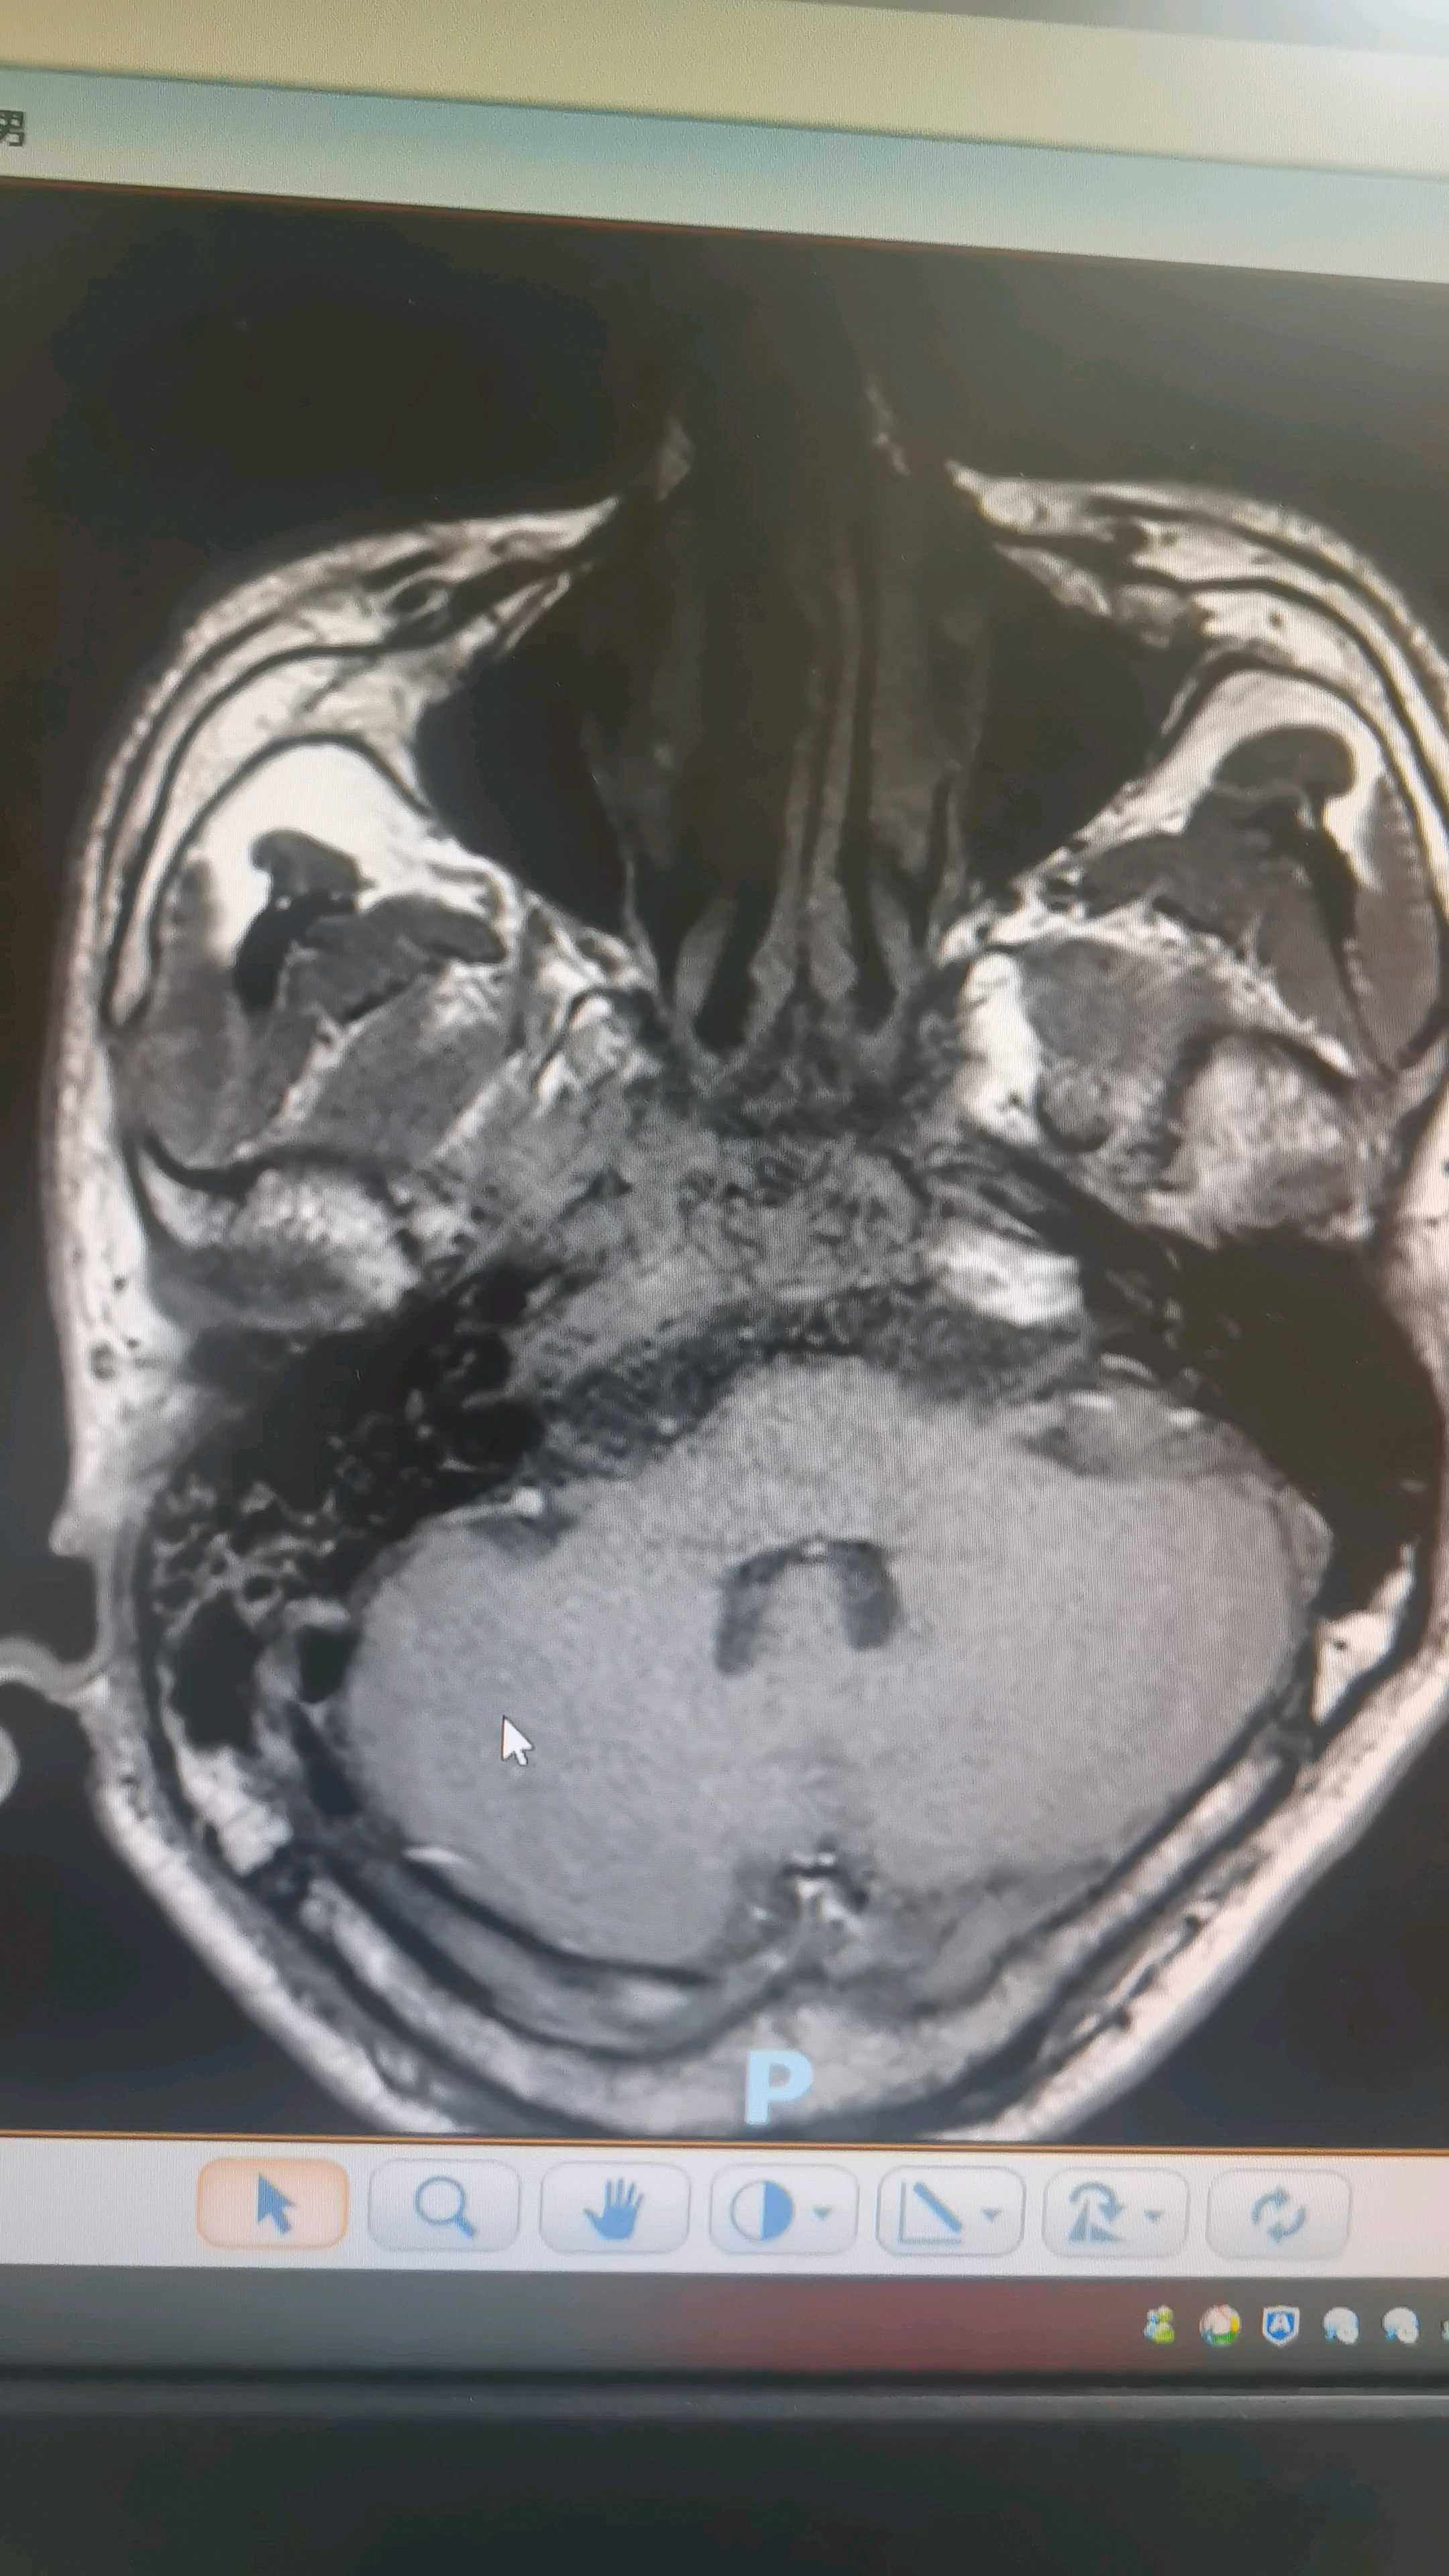

眼框mr